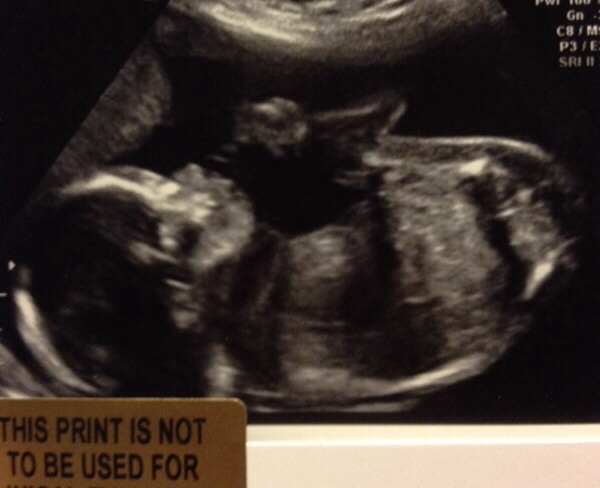

Any guesses boy or girl??

20 week scan